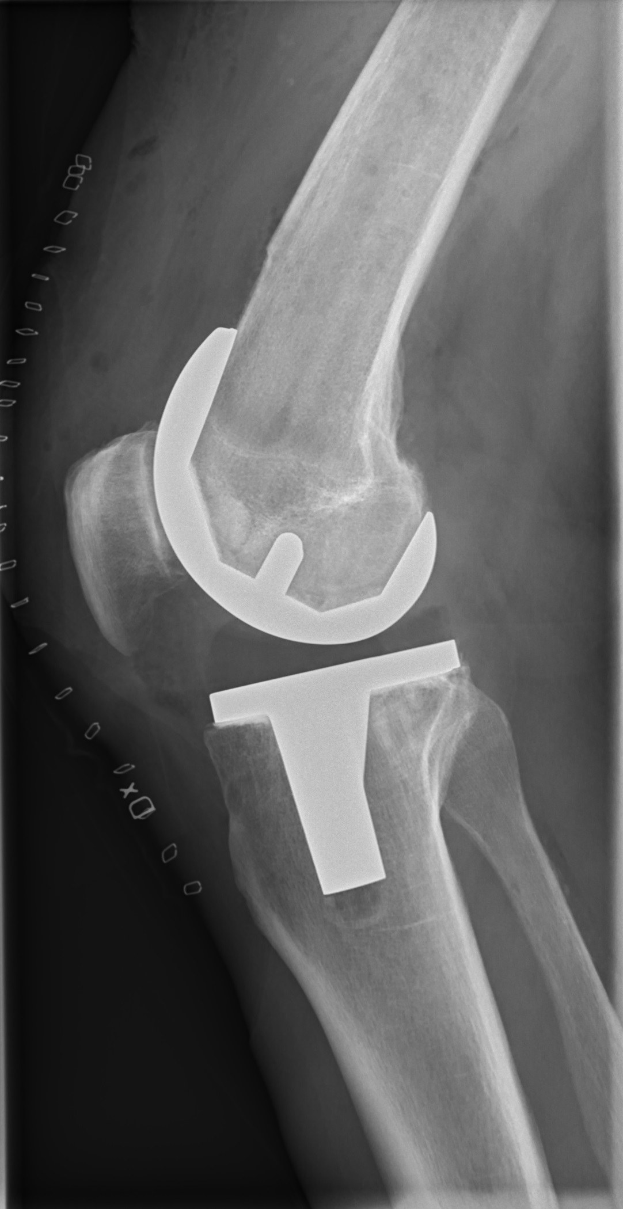

SC Paderborns Innenverteidiger Calvin Brackelmann wurde an einer Verkalkung im linken Oberschenkel operiert. Der 25-Jährige laboriert seit Mitte Oktober an wiederkehrenden Verletzungsrückschlägen, die ihn seither außer Gefecht gesetzt haben.